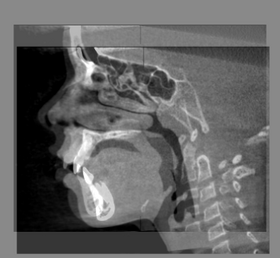

Baseline CBCT Scan - Input Scan

Follow up CBCT Scan - Input Scan

Baseline Input Scan + Followup Input Scan

Baseline and Followup CBCT Scans - Baseline and Followup CBCT Scans Registered - Baseline Input Scan + Output Scan